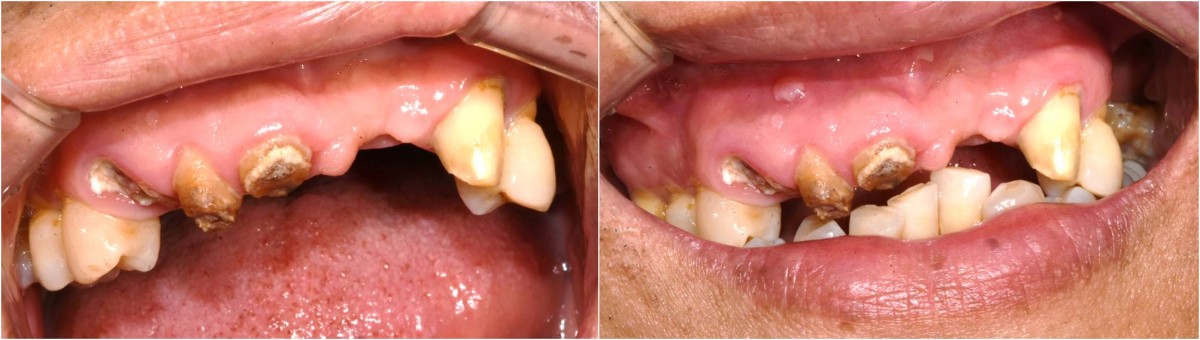

In the anterior maxilla, implant-supported fixed partial denture.

<GCpbc> A 58-year-old male is a patient undergoing implant installation in various parts. The old Br of the anterior maxilla has fallen

off and it is no longer possible to maintain it even temporarily, so a

treatment plan for the anterior teeth was made.